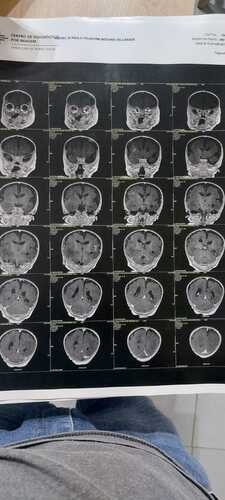

A nova ressonância mostrou que os dois lados do cérebro não se desenvolveram, o que infelizmente torna a cirurgia impossível.

🧠 Hemimegalencefalia parcial direita🧠 Displasia cerebelar direita e atrofia cerebelar esquerda

Essas condições afetam diretamente o desenvolvimento, o equilíbrio, a coordenação e causam crises frequentes. É como se o cérebro do Rafinha o travasse por dentro.